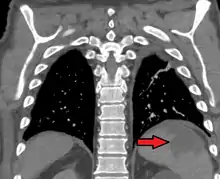

| Splenic infarct seen on CT | |

An abdominal CT scan is the most commonly used modality to confirm the diagnosis,[3] although abdominal ultrasound can also contribute.[5][6][7]